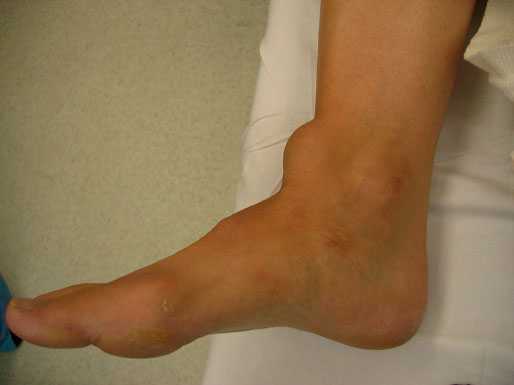

При локальном осмотре визуально отмечалась гипотрофия мышц задней поверхности левой голени. Положительный тест сжатия голени слева (симптом Томпсона). Окружность в верхней трети голеней: справа 35 см, слева 30 см. Сила мышц подошвенных сгибателей стоп (по шкале Ловвета) [2]: справа 5 баллов, слева 2 балла.

У данного пациента имеет место дисфункция сухожилия задней большеберцовой мышцы с развитием плоскостопия. Передний отдел стопы направлен наружу. Симптом «слишком много пальцев». При осмотре стопы сзади мы 3,4,5 палец стопы.